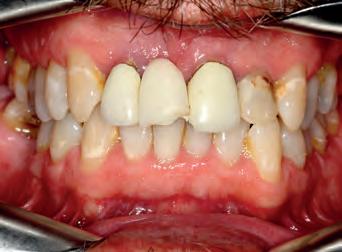

Patient: face before

A53 year old man attended complaining of pain from an existing bridge UR2 - UL2. It needed to be extracted because several roots were infected and would have required re-RCT, which the patient did not want to do. On closer inspection, the remaining teeth in the upper arch required some work as well (one RCT), but otherwise the teeth had a good prognosis.

The options were explained to the patient (implants, bridges/crowns/dentures) and the patient decided to save his remaining teeth. Written and verbal consent was obtained. We took clinical records and a series of DSLR photos and intraoral scanning with the Carestream 3600 intra oral scanner with scan flow software. The CS 3600 was chosen because of the comprehensive restorative features such as checking how much tooth structure has been removed compared to the pre-op tooth shape, as well as checking for any undercuts.

The decision was made, to extract the remaining upper incisors and make a temporary bridge from UR3 - UL3 in Luxatemp A3 with no immediate change to tooth shape or smile design.